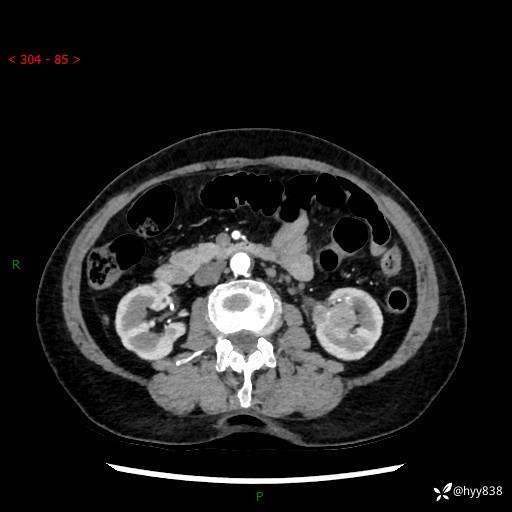

72岁/女,检查发现左肾占位1天。为了满足诊断,常规四期后,又加了延迟期-结果公布~

【患者信息】:72岁/女

【主诉】:检查发现左肾占位1天

【现病史及既往史】:患者于1天前检查发现左肾占位,无畏寒发热,无咳嗽咳痰,无腰腹部疼痛不适,无肉眼血尿、无尿频尿急症状,起病来,患者未行特殊治疗,为求进一步诊治,门诊以"左肾占位"收治入院。 发病来患者精神、饮食、睡眠良好,小便如上,大便正常,体重无明显变化。

【检查】:肾脏CT平扫+增强